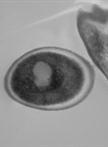

Candida auris, labeled an urgent threat by the CDC, shows significant resilience to treatments and disinfectants via biofilm formation, complicating treatment/disease management. The inconsistencies in biofilm architecture observed across studies hinder the understanding of its role in pathogenesis. Our novel in vitro technique cultivates C. auris biofilms on gelatin-coated coverslips, reliably producing multilayer biofilms with extracellular polymeric substances (EPS). This method, applicable to other Candida species like C. glabrata and C. albicans, is cost-effective and mimics the niche of biofilm formation. It is suitable for high-throughput drug screening and repurposing efforts, aiding in the development of new therapeutics. Our technique represents a significant advancement in Candida biofilm research, addressing the need for consistent, reproducible biofilm models. We detail a step-by-step procedure for creating a substratum for biofilm growth and measuring biofilm thickness using confocal laser scanning microscopy (CLSM) and ultrastructure by scanning electron microscopy (SEM). This method provides consistent outcomes across various Candida species.

To address these issues, we proposed a novel in vitro method for growing C. auris biofilms on gelatin-coated coverslips derived from bovine skin. Gelatin, a derivative of collagen, mimics the matrix of mammalian cells, thereby more closely replicating natural conditions. This method successfully forms heterogeneous, multilayered biofilms of C. auris. The architecture of these biofilms has been analyzed using scanning electron microscopy (SEM) and compared with previous studies [14–16]. Furthermore, the versatility and accuracy of this method have been demonstrated using confocal scanning laser microscopy (CSLM) to measure biofilm thickness. The application of this innovative in vitro technique is not only limited to C. auris biofilms but can also be used to study biofilm formation in other Candida species, such as Candida glabrata and Candida albicans. This method is a potent, cost-effective solution for large-scale drug screenings.